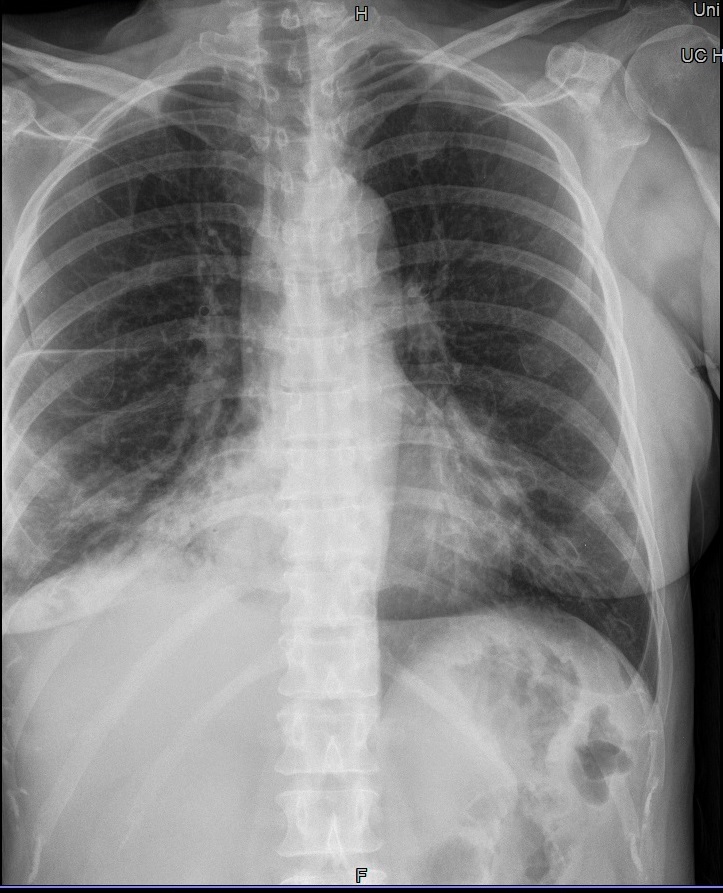

Schneidet der seitliche Filmrand die laterale Thoraxwand ab, evtl. durch zu schmales Filmformat oder unzureichend gute Positionierung, so wird der so wichtige Thorax-Zwerchfell-Winkel (Sinus phrenico-costalis) nicht abgebildet. Eine alte oder eine kleine frische Brustfellentzündung wird auf einer solchen Aufnahme übersehen.

Man muss den Patienten so stellen, dass der rechte und linke Kassettenrand noch seitlich vorstehen und die Blende nicht abschneidet.